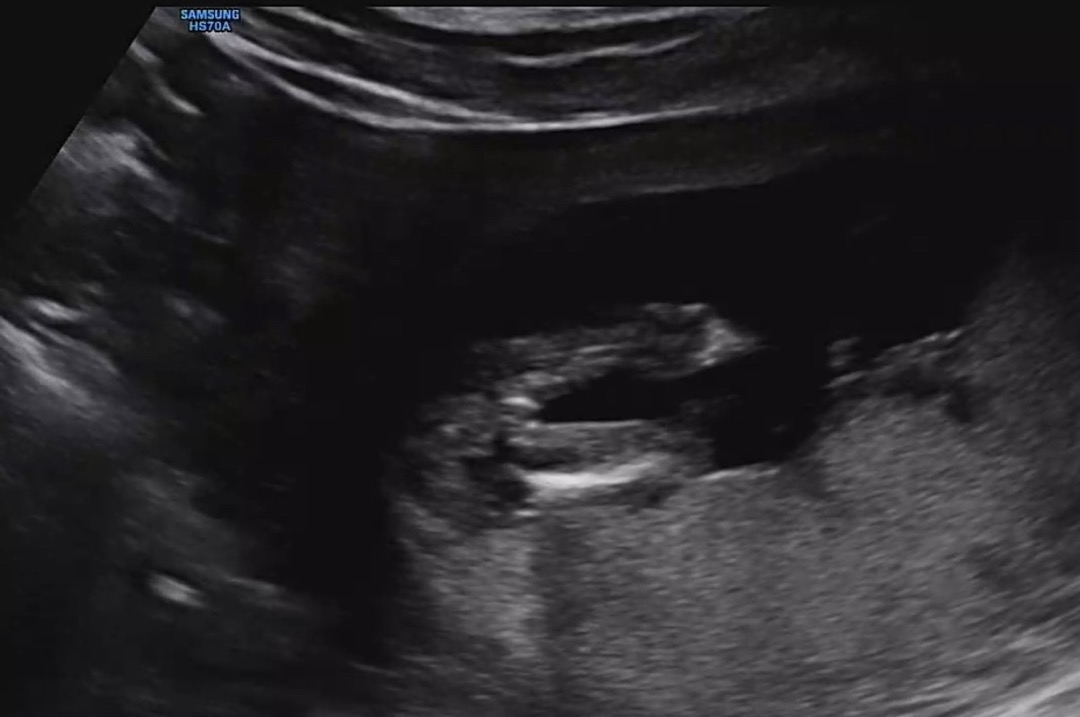

성별 드디어 나왔는데 🥲

애기 성별이 드디어 나왔는데 병원에서는 딸 같다고 하시는데 원래 딸이여도 튀어나와있다가 이정도면 서서히 들어갈거같다고 하시는데 다들 보시기에는 아들일거같나요 딸일거같나요ㅜㅜ 자꾸 딸인거 같으면서도 아들인거 같기도하고 헷갈리네요,,, ㅋㅋㅋㅋㅋㅋㅋㅎㅎ,,, 영상 보다보면 들어가있는거같기도하고 다시 나오는거같기도하고.,